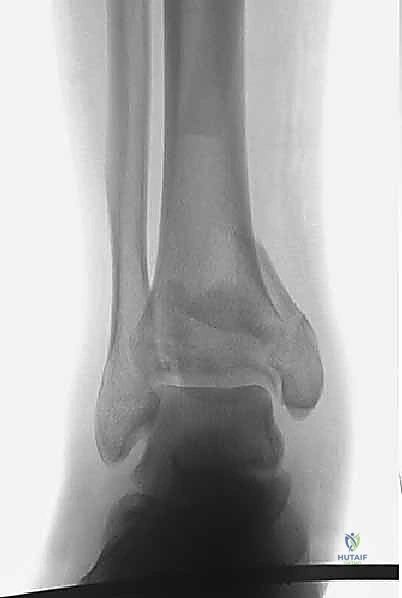

1. التصوير بالأشعة السينية التقليدية (X-Rays)

يتم أخذ صور من ثلاث زوايا (أمامية خلفية AP، جانبية Lateral، ومورتيس Mortise). تعطي هذه الصور فكرة عامة عن نمط الكسر، قصر الساق، ومدى انزياح العظام.